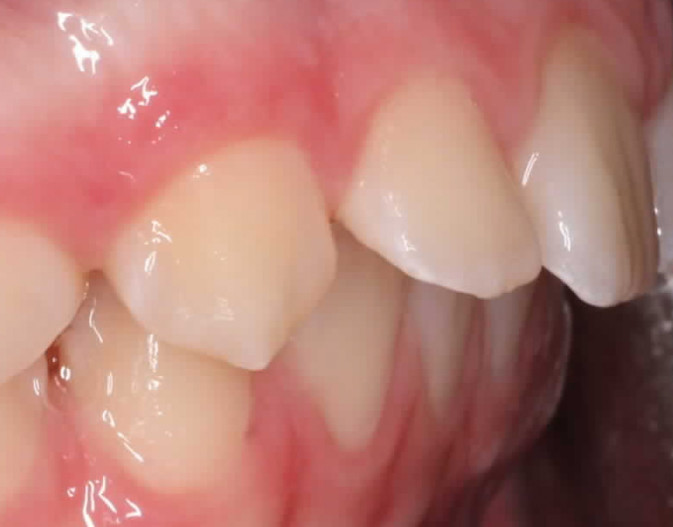

Klinisches Fallbeispiel 2 (Abb. 2a–y)

Distalbiss und tiefer Biss bei einem zwölfjährigen Mädchen. Die Behandlung erfolgte mit Invisalign und Precision Wings. Insgesamt waren zwei Schienensätze notwendig. Die Gesamtbehandlung dauerte 18 Monate.Bei der Planung des ClinCheck wurde der tiefe Biss vorwiegend über eine Intrusion der Unterkieferfront behoben, um die Lachlinie der Patientin nicht negativ zu beeinflussen. Die Oberkieferfront wurde nur retrudiert, jedoch vertikal nicht intrudiert. Während der Phase des Mandibular Advancement wurde die Wirkung der Precision Wings durch den Einsatz von Klasse II-Gummizügen unterstützt. Schlussendlich wurde auch der hängenden Okklusionsebene durch eine einseitige Intrusion der Molaren im ersten Quadranten Rechnung getragen.